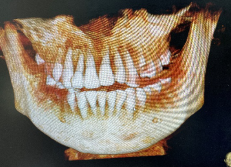

术后复诊CT

摘除固定板ct

通过一个多月的恢复治疗,小皓的四颗门牙再植成功。